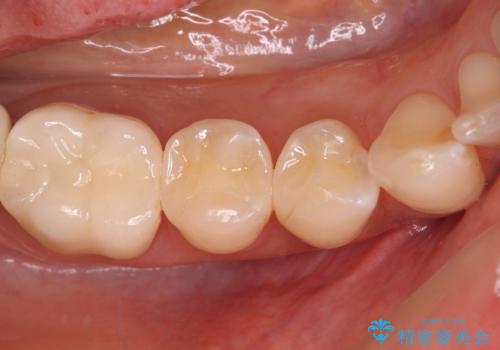

- 冷たいものがしみるとのことで来院された患者様です。

診査を行った結果、第一小臼歯にある樹脂の詰め物(コンポジットレジン)と歯の境目が痛みの原因であることが分かりました。

また、隣接する第二小臼歯も虫歯になっていることも分かったため、2歯を同時に治療するにしました。

下顎の目立つ位置であるため、セラミックインレーによる修復治療を行うこととしました。